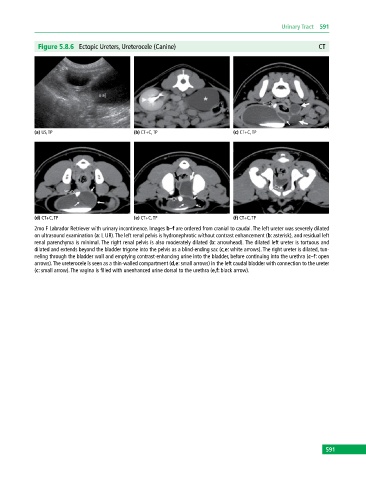

Figure 5.8.6 Ectopic Ureters, Ureterocele (Canine) CT

(a) US, TP (b) CT+C, TP (c) CT+C, TP

(d) CT+C, TP (e) CT+C, TP (f) CT+C, TP

2mo F Labrador Retriever with urinary incontinence. Images b–f are ordered from cranial to caudal. The left ureter was severely dilated

on ultrasound examination (a: L UR). The left renal pelvis is hydronephrotic without contrast enhancement (b: asterisk), and residual left

renal parenchyma is minimal. The right renal pelvis is also moderately dilated (b: arrowhead). The dilated left ureter is tortuous and

dilated and extends beyond the bladder trigone into the pelvis as a blind‐ending sac (c,e: white arrows). The right ureter is dilated, tun-

neling through the bladder wall and emptying contrast‐enhancing urine into the bladder, before continuing into the urethra (c–f: open

arrows). The ureterocele is seen as a thin‐walled compartment (d,e: small arrows) in the left caudal bladder with connection to the ureter

(c: small arrow). The vagina is filled with unenhanced urine dorsal to the urethra (e,f: black arrow).